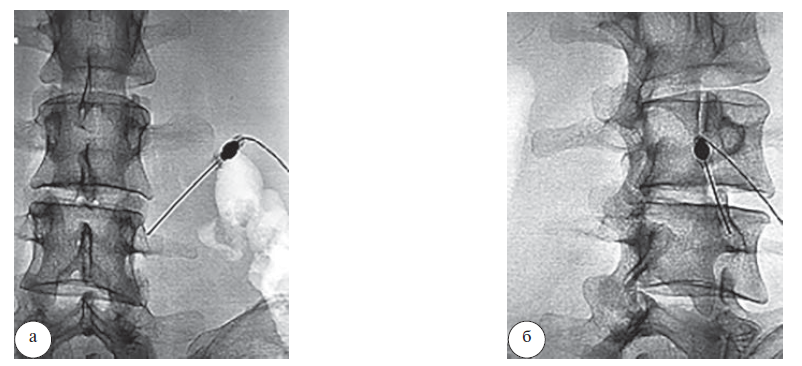

Радиочастотная абляция проводилась в условиях рентген-операционной под местной анестезией в положении больного лежа на животе. Необходимая точка воздействия – пересечение поперечного отростка и верхнего суставного отростка, где локализуется медиальная ветвь задней ветви спинномозгового нерва, иннервирующая межпозвонковый сустав (рис. 1).

Рис. 1. Интраоперационная спондилография при радиочастотной денервации межпозвонковых суставов: а – прямая проекция; б – боковая проекция

Для подтверждения правильности положения кончика канюли всем пациентам были проведены последовательно 2 контрольные стимуляции: сенсорная и моторная. При получении положительного результата стимуляции осуществлялось местное обезболивание и проводилась термическая РЧА со следующими показателями: длительность воздействия – 90 с, температура – 80–90°С.